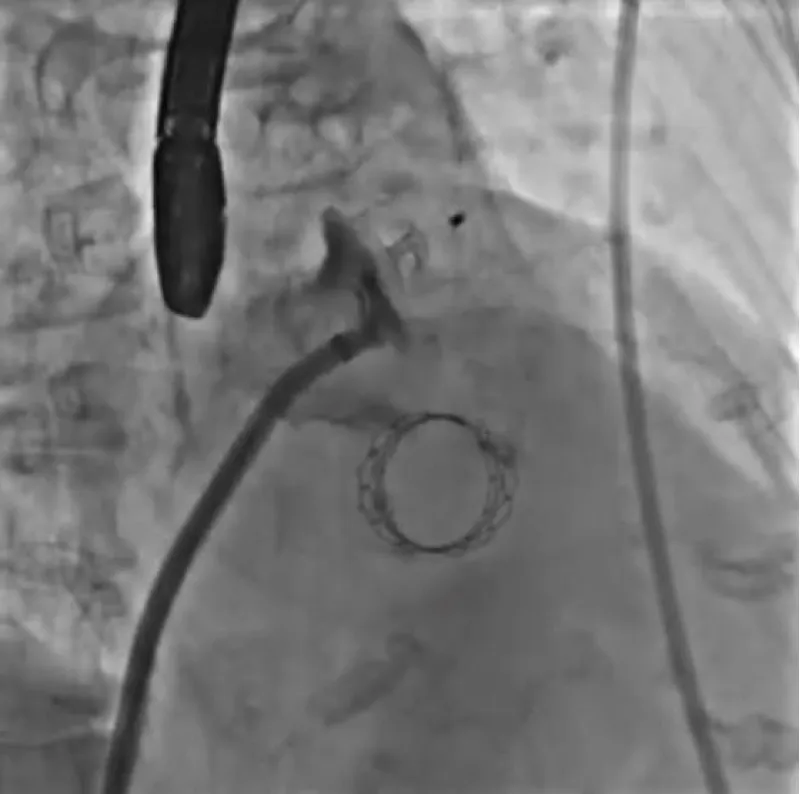

Download Image

Figure 13: Sapien 3 23 mm.

With the support of deep sedation, an angio-guided right femoral access was obtained, and a 12F introducer was advanced. We crossed the aortic valve with an Amplatzer left 1 catheter with a 0.035” wire and exchanged the wire with an extra-stiff Safari. We performed aortic Valvuloplasty with a Nucleus balloon 18 x 40 mm. (Figure 7) Then, we exchanged the wire and advanced an IMPELLA CP device, starting a protected PCI on LM. (Figure 8) An EBU 4.0 catheter was advanced, the stenosis was crossed on the Left Main (LM) and mid-Left Anterior Descending artery (LAD) using a BMW guide wire, and with the aid of a microcatheter a 0.014” Rotawire was positioned, followed by rotational atherectomy using a 1.5 mm burr on LM and mid LAD, (Figure 9) and a 2.0 mm burr on LM alone (Figure 10). This was followed by predilation with a 2.5 x 20 mm SC balloon and the implantation of a 2.5 x 32 mm Synergy drug-eluting stent (Figure 11). Then, the Left Main was predilated with a 3.5 x 12 mm NC balloon, and a 4.0 x 15 mm Xience Sierra drug-eluting stent was implanted and post-dilated with a 4.5 x 8 mm SC balloon (Figure 12). Immediate angiographic control confirmed a successful result. Then we removed the IMPELLA CP device and advanced a 14F e-sheath Edwards on the right femoral artery, crossed the aortic valve with a Safari extra-stiff wire, and performed a Sapien 3 23 mm valve implantation with a good angiographic result (Figure 13). Post-procedural echocardiographic and angiographic assessment confirmed the valve was correctly positioned, with no significant gradient and a minimal residual leak. The procedure was uneventful, and the patient was discharged on the fourth day with triple therapy: Aspirin 100 mg once daily, Clopidogrel 75 mg once daily, and Apixaban 2.5 mg twice daily. At the quarterly follow-up, the patient reported hospitalization for anemia, requiring a transfusion of 3 units of packed red blood cells. Endoscopic exams were negative, and hypochromic, normocytic anemia persisted. Given the patient’s CHA2D2-VASc score of 5, HAS-BLED score of 4, and recent dual Drug-Eluting Stent (DES) implantation, she was admitted for left atrial appendage percutaneous closure. Before this procedure, a repeat coronary angiography showed good results in the previously implanted stents (Figure 14). Subsequently, through a right femoral percutaneous approach using a 12F introducer, a 22 mm Amulet device was positioned for left atrial appendage closure (Figure 15). The procedure was completed without complications. At the 4-year follow-up, the patient presented in good hemodynamic status, with an echocardiographic ejection fraction of 55%. She continued on clopidogrel 75 mg once daily therapy.